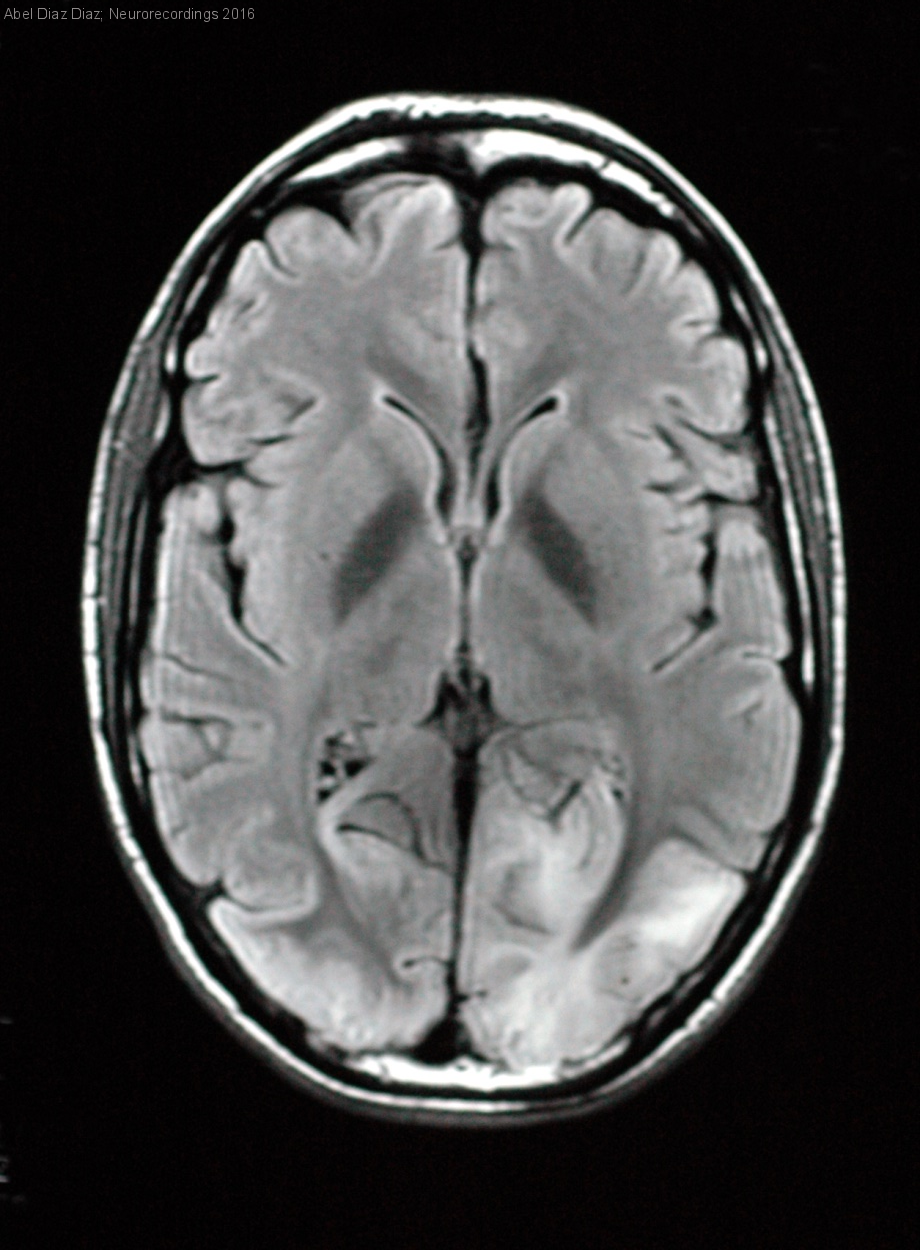

Hombre | 20 años

Diagnóstico final: Síndrome MELAS

Varón de 20 años con antecedentes personales de retraso del crecimiento y crisis comiciales desde la infancia y familiares de fallecimiento de abuela materna por enfermedad muscular no filiada que ingresa por ceguera bilateral de origen cortical. A la...